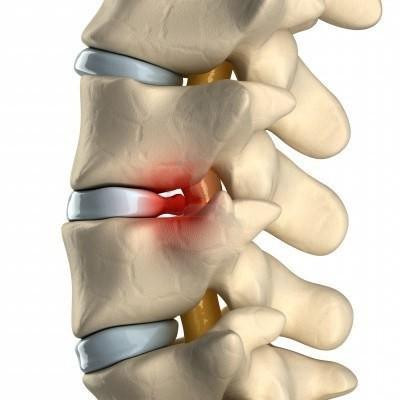

Межпозвоночная грыжа

Поясничные грыжи обычно находятся между третьим, четвертым и пятым поясничными позвонками и между пятым позвонком и крестцом. Зачастую грыжей защемляются нервы, ведущие в нижние конечности. Боль при межпозвонковых грыжах острая. Больному тяжело нагибаться, вставать, порой даже лежать на ровной поверхности.

На самом деле, боль в паху и резкая боль в пояснице не предполагают обязательное наличие межпозвоночной грыжи.

Если врач все же поставил такой диагноз, то терапия должна быть назначена незамедлительно.

В курс терапии входят:

- Анальгетики – Ортофен, Нурофен, Вольтарен. Предпочтение отдается мазям.

- Препараты, содержащие витамины С и В.

- Препараты для усиления циркуляции крови.

При межпозвоночной грыже больному нужно придерживаться диеты, установленной доктором. Как правило, в рацион должно входить большое количество продуктов, содержащих кальций.